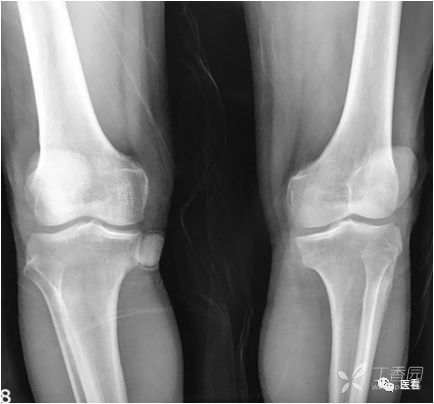

肺坠积效应

由于血液因引力作用向近地侧沉积,因此两肺下叶背侧胸膜下带血液相对较多,双肺后部肺野密度增高(箭示),称之为坠积效应。在老年人及长期卧床者尤其明显。如果不认识可能误认 为肺内炎症或肺间质纤维化。